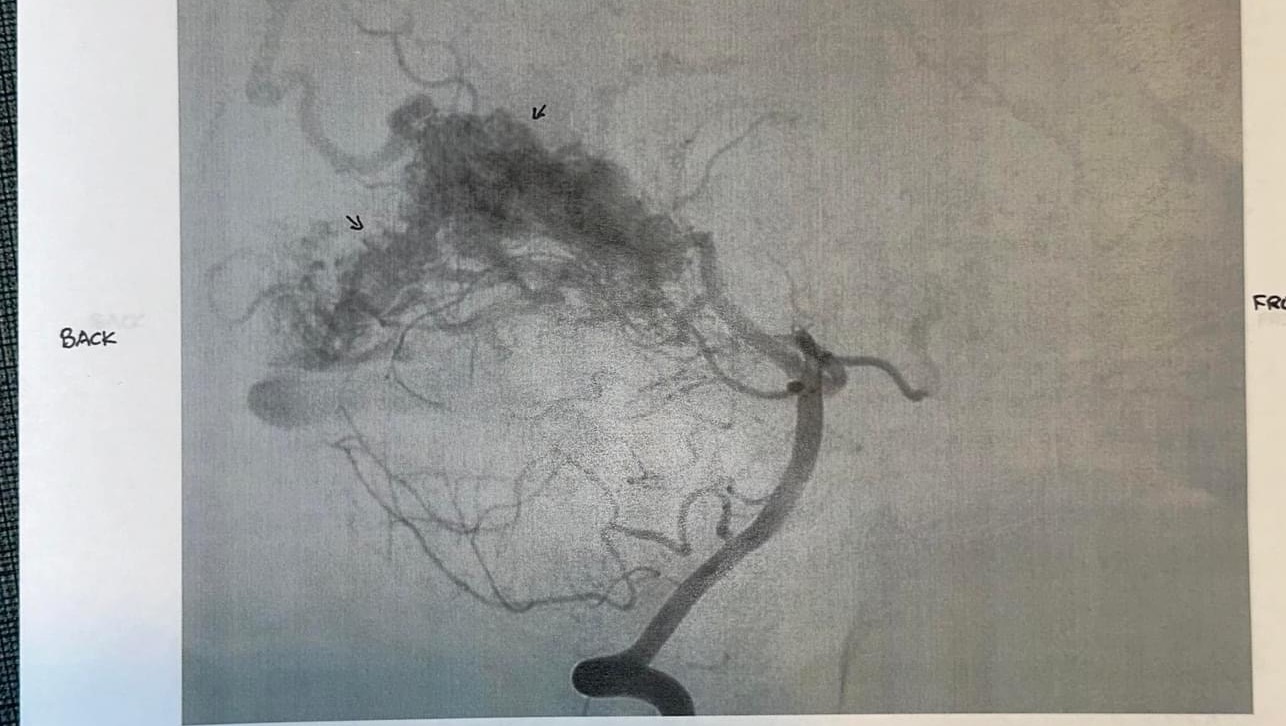

Early in December, she began complaining of a severe headache. Headaches are nothing new for Kenzie. She has had intermittent migraines with “visual auras”over the last several years. But after 9 days of failed outpatient treatment, we headed to the ER, where an MRI revealed a large (grade 4) Occipital AVM.

AVMs or Arteriosclerosis-Venous Malformations are an area of blood vessels that, instead of forming in straight lines, form in a bundle (or, as Kenzie likes to say, a knot). Instead of having clear high-pressure tolerant arteries and low pressure venous drainage, these vessels are mismatched and hopelessly tangled. Because of this malformation, there is also no capillary bed within her “knot” to allow oxygen and nutrient to exchange. AVMs are the leading cause of stroke in the pediatric population and are often not discovered unless one of those vessels ruptures and bleeds.

We were quickly transferred to OHSU and placed in the amazing care of their neurosurgical team for ongoing testing. This included a brain angiogram and that showed her AVM was larger than originally thought, measuring about 5cm x 3cm. During that hospitalization, it was discovered that her AVM has already started to cause her permanent side effects. She has lost a good portion of her left upper field of vision in both eyes.

We were sent home with some decisions to make… Treatment options for AVM include taking a “wait and see” approach (The risk of AVM rupture is about 2-4% per year, and we have been told that due to the nature of her particular lesion, rupture would cause catastrophic damage possibly extending beyond just her sight), Embolization (not an option for hers due to the size and the number of feeding vessels), Radio-surgery (aka Gamma Knife, still not a first line option for her because of the amount of radiation it would require, not to mention it only provides a 70% success rate over the course of 3-5 years. This option may be used as an adjunct therapy if they are not able to safely remove her entire lesion during the initial surgery), and Neurosurgery (which is the plan). Her surgical date is set for 2/6/24 and the surgery itself is estimated to be >12 hours in length.